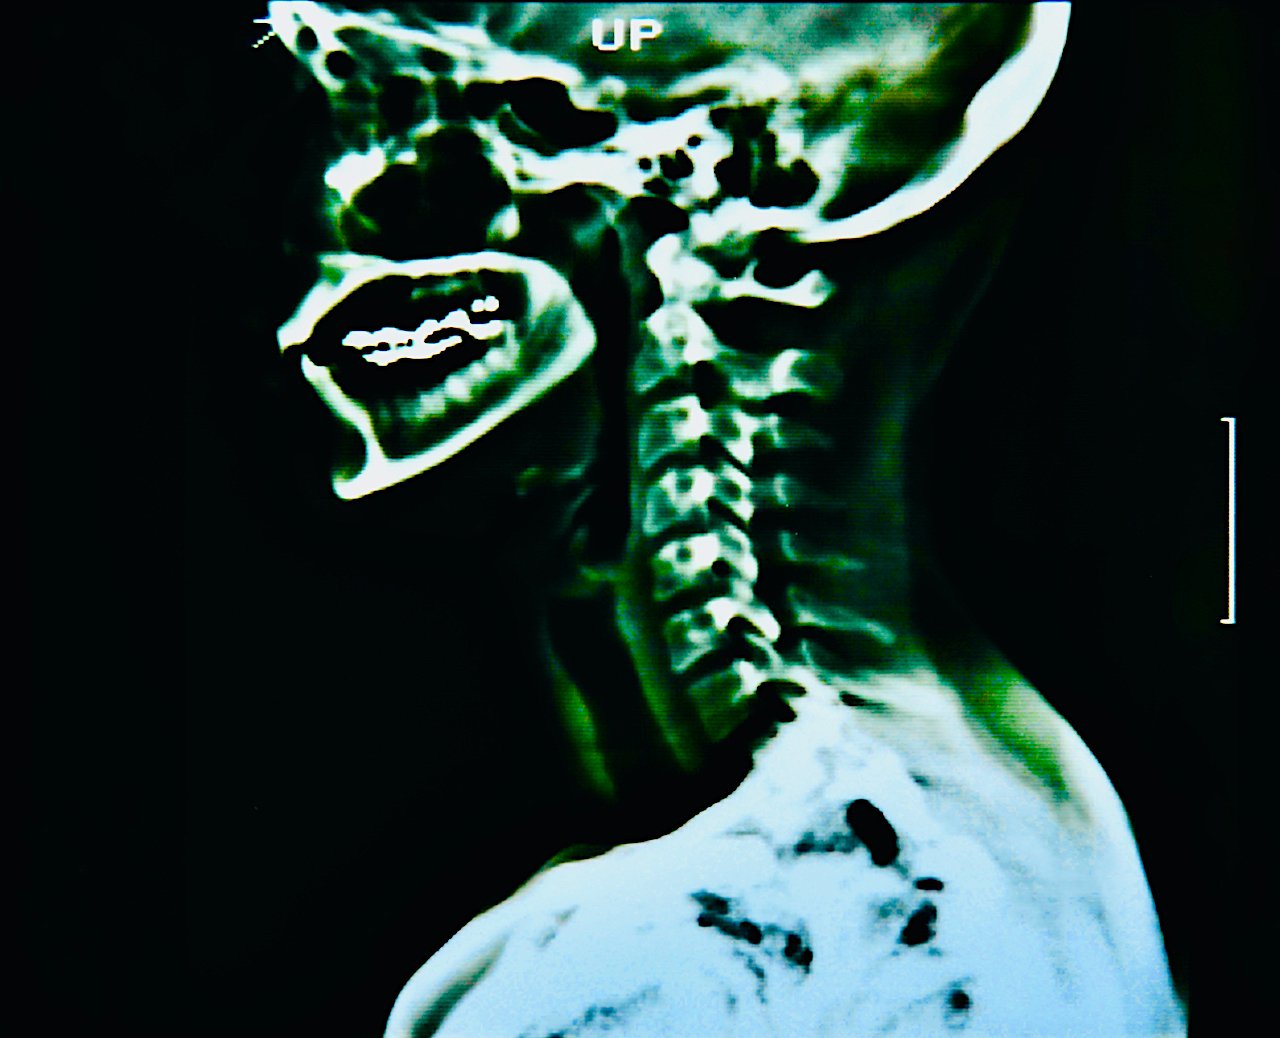

saturday night fever (boy meets girl diptych)

Selected for July/Aug 2022 exhibition in Art No.23’s Barcelona gallery.